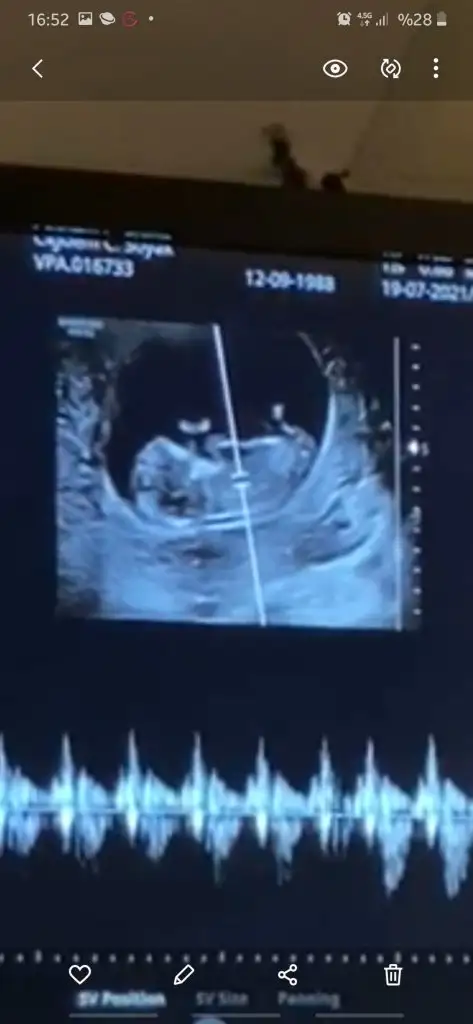

• Screenshot_20210205-135111_Video Player.webp

Screenshot_20210205-135111_Video Player.webp

10,8 KB · Görüntüleme: 61